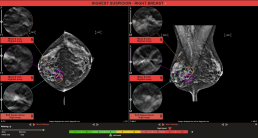

MammoScreen® : Deux masses co-localisées avec des calcifications identifiées dans les vues RIGHT CC et RIGHT MLO avec un score MammoScreen™ de 9. Une lésion des tissus mous co-localisée dans le RIGHT CC et le RIGHT MLO avec un score de 8, toutes ces observations sont prises en compte. En outre, MammoScreen a identifié le kyste bénin dans le sein gauche et lui a donné un faible score de 3.